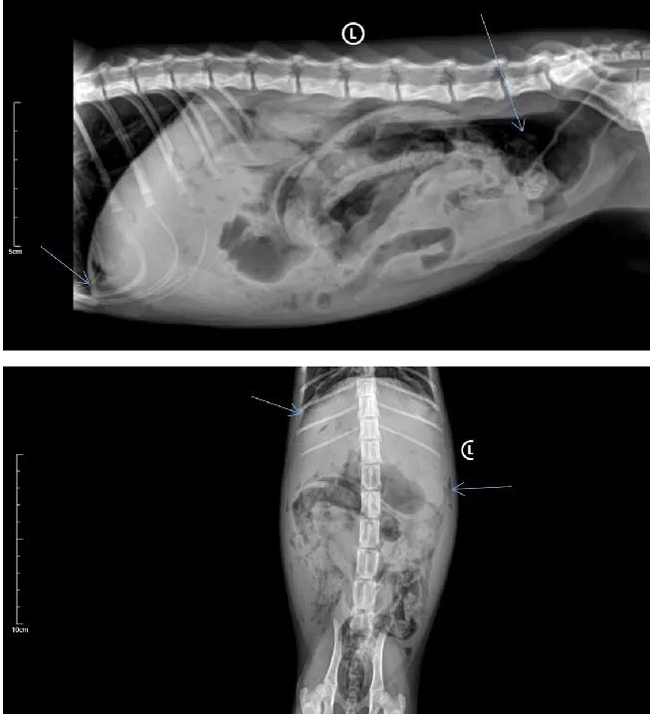

一例猫胃穿孔的诊治(图)

上午10点X线检查:

结果:气腹,可见肝前区腹侧和结肠背侧有气体影像